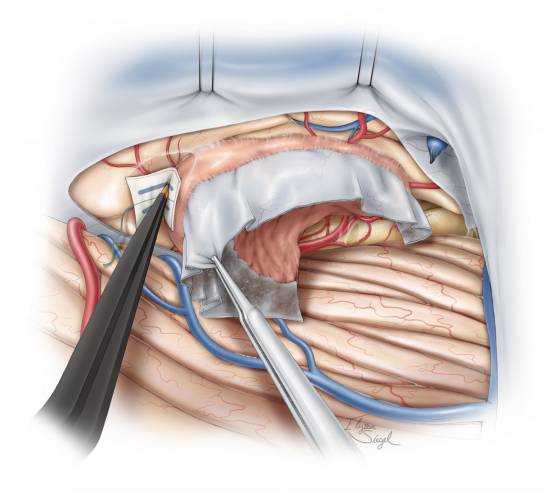

图12. 在对肿瘤进行足够的内减压后,再分离瘤壁与周围如枕叶底部和颞叶后部等神经血管组织,在这分离过程中注意保护大脑后动脉。

图13. 小块的脑棉垫片用来逐渐垫开肿瘤与瘤周组织。这一操作与处理凸面脑膜瘤类似。经天幕入路本质上是将一个中线区域的天幕脑膜瘤变为凸面脑膜瘤。

图14. 经天幕入路创造了一条直接到达枕叶底部和颞叶后方的通道。如果切除肿瘤和侵蚀的天幕可以达到Simpson I级切除,这会使得肿瘤复发率很低。在这一区域的轴内肿瘤(intraaxial tumor)也可通过这一入路切除。